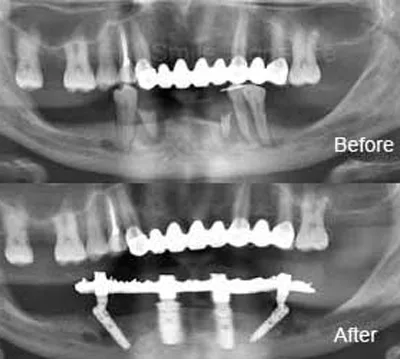

การฝังรากแบบนี้เป็นวิธีที่ทำกันโดยทั่วไป สามารถทำได้เกือบทุกกรณี สามารถฝังรากฟันเทียมชนิดนี้เพื่อทดแทนฟันที่สูญเสียไปเพียงซี่เดียว หลายซี่ หรืออาจจะทั้งปาก

โดยปกติแล้วการฝังรากฟันเทียมแบบทั่วไปนั้นแบ่งออกเป็น 2 ขั้นตอน ระยะห่างแต่ละขั้นตอนนั้นห่างกันประมาณ 2-6 เดือน

การฝังรากฟันเทียมแบบทั่วไปสามารถทำได้ในสภาพกระดูกขากรรไกรของคนไข้ส่วนใหญ่ แต่หากในบางกรณีที่คนไข้กระขากรรไกรมีความบางกว่าปกติ หรือมีการสูญเสียกระดูกบริเวณที่จะทำหารฝังรากฟันเทียม ทันตแพทย์เฉพาะทางอาจพิจารณาให้ปลูกกระดูกก่อนรับการฝังรากฟันเทียม เพื่อให้กระดูกบริเวณนั้นมีความหนา และแข็งแรงพอรองรับการฝังรากฟันเทียม